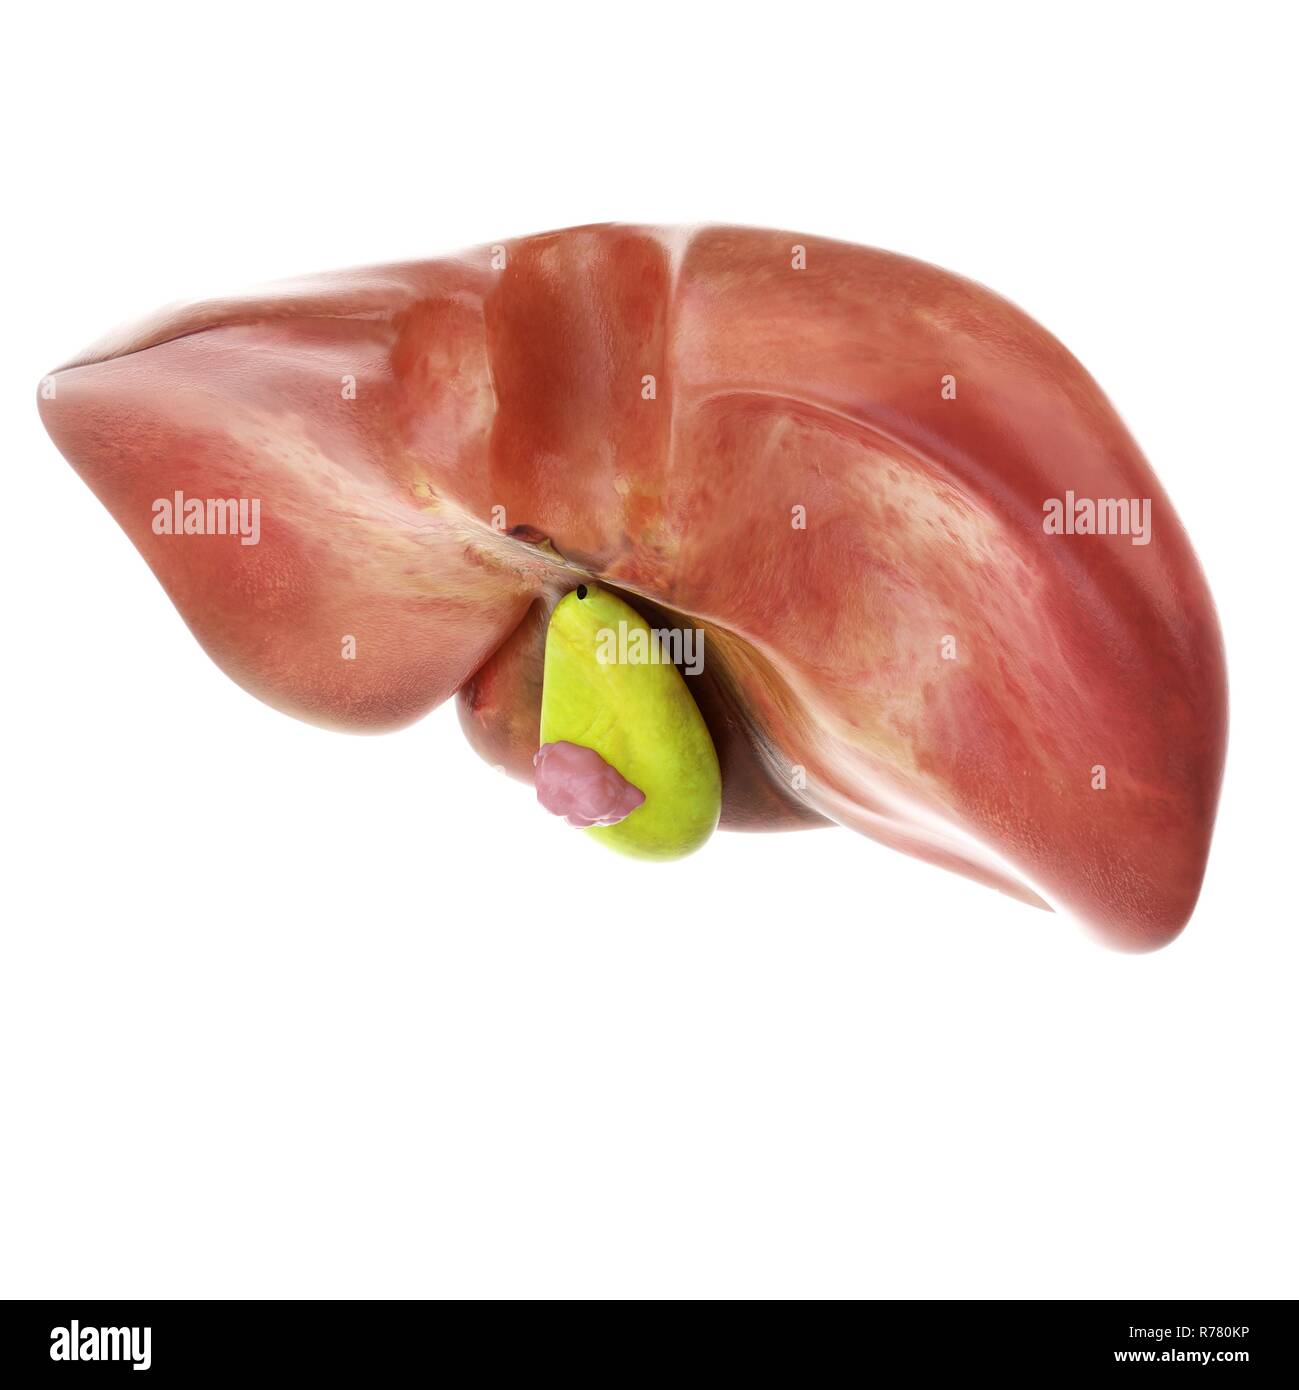

La vésicule biliaire joue un rôle essentiel dans la digestion des graisses. Un dysfonctionnement, causé par une tumeur, perturbe ce processus. Plusieurs symptômes digestifs peuvent alors apparaître.

La présence d'une masse palpable dans l'abdomen supérieur droit est un signe avancé de la maladie. Elle indique une tumeur de taille importante.